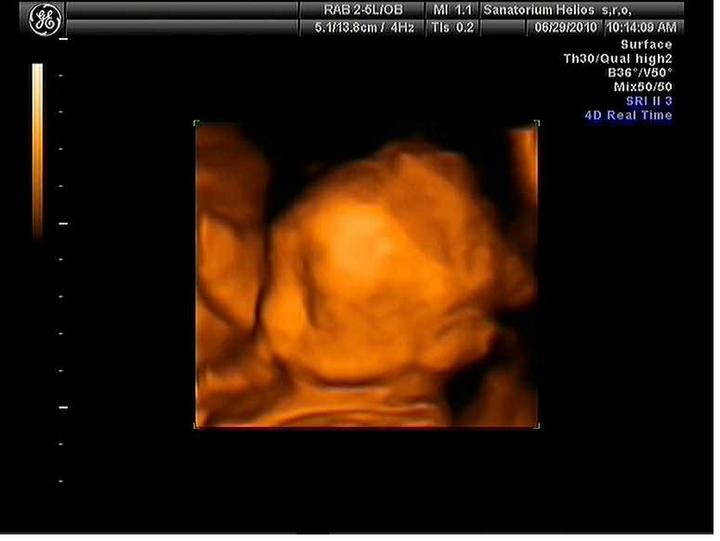

Triple test negativnííí 🙂 hurááá 🙂